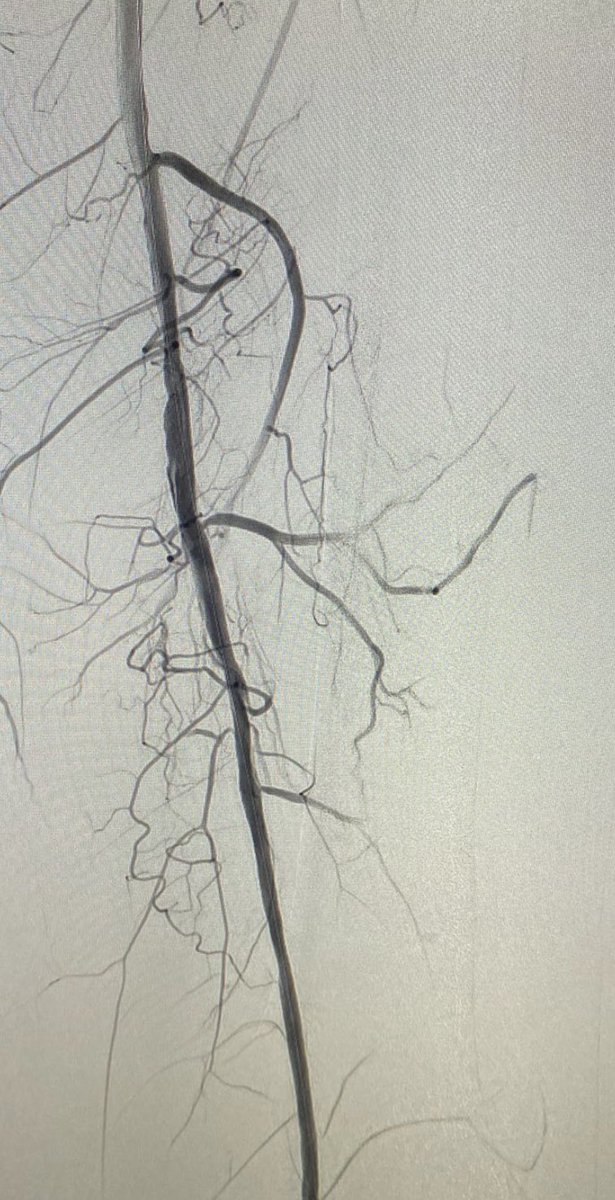

Excited to share our latest publication. Honored to work with an amazing team under the guidance of Dr. Thamer Albilasi | ثامر البلعاسي and Dr. د.حاتم الزهراني Dr.Hatem ALZAHRANI. Grateful for the opportunity 🙏🏻 #ENT link.springer.com/article/10.100…